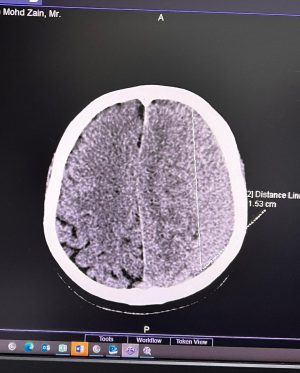

Caption : Kalau anyone you know jatuh kepala terhentak, luaran memang takde apa tapi dalaman maybe boleh jadi pendarahan perlahan. Sejurus dari terjatuh, bila check X-Ray dan CT scan it will tell you nothing, semua clear saja, but 2-3weeks later could turn into your biggest nightmare when the blood has flooded a big part of your brain. My dad realised something was wrong hampir sebulan lepas jatuh, when suddenly he couldn’t really move his right leg. Macam lagging. Sebab dia jatuh terhentak dahi kiri, bila anggota belah kanan yang terjejas, we knew it must be the brain. I picked him up and asked about his very very recent trip to Acheh, he said “Bila Daddy pergi Acheh?”. Ya Allah this very man, is my dad, someone who was very sharp and opinionated, tiba-tiba sangat blur dan slow, jawab sepatah-sepatah. So I spent the whole day uruskan dia, consulted two specialists and one neurosurgeon and when he is finally admitted that night to prepare him for his surgery the following day, he told the family “Daddy tadi drive sendiri datang sini”. My heart sank, I was frantic with worry — takutnya lagi lambat ni lagi banyak memori dia hilang. The brain surgery went well atas izin Allah, thank you to everyone involved. Doktor kata kalau lewat sikit je lagi memang boleh hilang keupayaan bercakap, keupayaan bernafas dan seterusnya koma, sebab otak dah compressed terlalu banyak darah. I jot this here as a reminder for all of us to always jangan tangguh-tangguh kalau hati dah tergerak. Daddy masih tak ingat I bawak dia pi hospital hari tu. Nasib baik kita selfie.Likes : 168141

Caption : Kalau anyone you know jatuh kepala terhentak, luaran memang takde apa tapi dalaman maybe boleh jadi pendarahan perlahan. Sejurus dari terjatuh, bila check X-Ray dan CT scan it will tell you nothing, semua clear saja, but 2-3weeks later could turn into your biggest nightmare when the blood has flooded a big part of your brain. My dad realised something was wrong hampir sebulan lepas jatuh, when suddenly he couldn’t really move his right leg. Macam lagging. Sebab dia jatuh terhentak dahi kiri, bila anggota belah kanan yang terjejas, we knew it must be the brain. I picked him up and asked about his very very recent trip to Acheh, he said “Bila Daddy pergi Acheh?”. Ya Allah this very man, is my dad, someone who was very sharp and opinionated, tiba-tiba sangat blur dan slow, jawab sepatah-sepatah. So I spent the whole day uruskan dia, consulted two specialists and one neurosurgeon and when he is finally admitted that night to prepare him for his surgery the following day, he told the family “Daddy tadi drive sendiri datang sini”. My heart sank, I was frantic with worry — takutnya lagi lambat ni lagi banyak memori dia hilang. The brain surgery went well atas izin Allah, thank you to everyone involved. Doktor kata kalau lewat sikit je lagi memang boleh hilang keupayaan bercakap, keupayaan bernafas dan seterusnya koma, sebab otak dah compressed terlalu banyak darah. I jot this here as a reminder for all of us to always jangan tangguh-tangguh kalau hati dah tergerak. Daddy masih tak ingat I bawak dia pi hospital hari tu. Nasib baik kita selfie.Likes : 168141

Caption : Kalau anyone you know jatuh kepala terhentak, luaran memang takde apa tapi dalaman maybe boleh jadi pendarahan perlahan. Sejurus dari terjatuh, bila check X-Ray dan CT scan it will tell you nothing, semua clear saja, but 2-3weeks later could turn into your biggest nightmare when the blood has flooded a big part of your brain. My dad realised something was wrong hampir sebulan lepas jatuh, when suddenly he couldn’t really move his right leg. Macam lagging. Sebab dia jatuh terhentak dahi kiri, bila anggota belah kanan yang terjejas, we knew it must be the brain. I picked him up and asked about his very very recent trip to Acheh, he said “Bila Daddy pergi Acheh?”. Ya Allah this very man, is my dad, someone who was very sharp and opinionated, tiba-tiba sangat blur dan slow, jawab sepatah-sepatah. So I spent the whole day uruskan dia, consulted two specialists and one neurosurgeon and when he is finally admitted that night to prepare him for his surgery the following day, he told the family “Daddy tadi drive sendiri datang sini”. My heart sank, I was frantic with worry — takutnya lagi lambat ni lagi banyak memori dia hilang. The brain surgery went well atas izin Allah, thank you to everyone involved. Doktor kata kalau lewat sikit je lagi memang boleh hilang keupayaan bercakap, keupayaan bernafas dan seterusnya koma, sebab otak dah compressed terlalu banyak darah. I jot this here as a reminder for all of us to always jangan tangguh-tangguh kalau hati dah tergerak. Daddy masih tak ingat I bawak dia pi hospital hari tu. Nasib baik kita selfie.Likes : 168141

Caption : Kalau anyone you know jatuh kepala terhentak, luaran memang takde apa tapi dalaman maybe boleh jadi pendarahan perlahan. Sejurus dari terjatuh, bila check X-Ray dan CT scan it will tell you nothing, semua clear saja, but 2-3weeks later could turn into your biggest nightmare when the blood has flooded a big part of your brain. My dad realised something was wrong hampir sebulan lepas jatuh, when suddenly he couldn’t really move his right leg. Macam lagging. Sebab dia jatuh terhentak dahi kiri, bila anggota belah kanan yang terjejas, we knew it must be the brain. I picked him up and asked about his very very recent trip to Acheh, he said “Bila Daddy pergi Acheh?”. Ya Allah this very man, is my dad, someone who was very sharp and opinionated, tiba-tiba sangat blur dan slow, jawab sepatah-sepatah. So I spent the whole day uruskan dia, consulted two specialists and one neurosurgeon and when he is finally admitted that night to prepare him for his surgery the following day, he told the family “Daddy tadi drive sendiri datang sini”. My heart sank, I was frantic with worry — takutnya lagi lambat ni lagi banyak memori dia hilang. The brain surgery went well atas izin Allah, thank you to everyone involved. Doktor kata kalau lewat sikit je lagi memang boleh hilang keupayaan bercakap, keupayaan bernafas dan seterusnya koma, sebab otak dah compressed terlalu banyak darah. I jot this here as a reminder for all of us to always jangan tangguh-tangguh kalau hati dah tergerak. Daddy masih tak ingat I bawak dia pi hospital hari tu. Nasib baik kita selfie.Likes : 168141

Caption : Kalau anyone you know jatuh kepala terhentak, luaran memang takde apa tapi dalaman maybe boleh jadi pendarahan perlahan. Sejurus dari terjatuh, bila check X-Ray dan CT scan it will tell you nothing, semua clear saja, but 2-3weeks later could turn into your biggest nightmare when the blood has flooded a big part of your brain. My dad realised something was wrong hampir sebulan lepas jatuh, when suddenly he couldn’t really move his right leg. Macam lagging. Sebab dia jatuh terhentak dahi kiri, bila anggota belah kanan yang terjejas, we knew it must be the brain. I picked him up and asked about his very very recent trip to Acheh, he said “Bila Daddy pergi Acheh?”. Ya Allah this very man, is my dad, someone who was very sharp and opinionated, tiba-tiba sangat blur dan slow, jawab sepatah-sepatah. So I spent the whole day uruskan dia, consulted two specialists and one neurosurgeon and when he is finally admitted that night to prepare him for his surgery the following day, he told the family “Daddy tadi drive sendiri datang sini”. My heart sank, I was frantic with worry — takutnya lagi lambat ni lagi banyak memori dia hilang. The brain surgery went well atas izin Allah, thank you to everyone involved. Doktor kata kalau lewat sikit je lagi memang boleh hilang keupayaan bercakap, keupayaan bernafas dan seterusnya koma, sebab otak dah compressed terlalu banyak darah. I jot this here as a reminder for all of us to always jangan tangguh-tangguh kalau hati dah tergerak. Daddy masih tak ingat I bawak dia pi hospital hari tu. Nasib baik kita selfie.Likes : 168141

Caption : Kalau anyone you know jatuh kepala terhentak, luaran memang takde apa tapi dalaman maybe boleh jadi pendarahan perlahan. Sejurus dari terjatuh, bila check X-Ray dan CT scan it will tell you nothing, semua clear saja, but 2-3weeks later could turn into your biggest nightmare when the blood has flooded a big part of your brain. My dad realised something was wrong hampir sebulan lepas jatuh, when suddenly he couldn’t really move his right leg. Macam lagging. Sebab dia jatuh terhentak dahi kiri, bila anggota belah kanan yang terjejas, we knew it must be the brain. I picked him up and asked about his very very recent trip to Acheh, he said “Bila Daddy pergi Acheh?”. Ya Allah this very man, is my dad, someone who was very sharp and opinionated, tiba-tiba sangat blur dan slow, jawab sepatah-sepatah. So I spent the whole day uruskan dia, consulted two specialists and one neurosurgeon and when he is finally admitted that night to prepare him for his surgery the following day, he told the family “Daddy tadi drive sendiri datang sini”. My heart sank, I was frantic with worry — takutnya lagi lambat ni lagi banyak memori dia hilang. The brain surgery went well atas izin Allah, thank you to everyone involved. Doktor kata kalau lewat sikit je lagi memang boleh hilang keupayaan bercakap, keupayaan bernafas dan seterusnya koma, sebab otak dah compressed terlalu banyak darah. I jot this here as a reminder for all of us to always jangan tangguh-tangguh kalau hati dah tergerak. Daddy masih tak ingat I bawak dia pi hospital hari tu. Nasib baik kita selfie.Likes : 168141

Caption : Kalau anyone you know jatuh kepala terhentak, luaran memang takde apa tapi dalaman maybe boleh jadi pendarahan perlahan. Sejurus dari terjatuh, bila check X-Ray dan CT scan it will tell you nothing, semua clear saja, but 2-3weeks later could turn into your biggest nightmare when the blood has flooded a big part of your brain. My dad realised something was wrong hampir sebulan lepas jatuh, when suddenly he couldn’t really move his right leg. Macam lagging. Sebab dia jatuh terhentak dahi kiri, bila anggota belah kanan yang terjejas, we knew it must be the brain. I picked him up and asked about his very very recent trip to Acheh, he said “Bila Daddy pergi Acheh?”. Ya Allah this very man, is my dad, someone who was very sharp and opinionated, tiba-tiba sangat blur dan slow, jawab sepatah-sepatah. So I spent the whole day uruskan dia, consulted two specialists and one neurosurgeon and when he is finally admitted that night to prepare him for his surgery the following day, he told the family “Daddy tadi drive sendiri datang sini”. My heart sank, I was frantic with worry — takutnya lagi lambat ni lagi banyak memori dia hilang. The brain surgery went well atas izin Allah, thank you to everyone involved. Doktor kata kalau lewat sikit je lagi memang boleh hilang keupayaan bercakap, keupayaan bernafas dan seterusnya koma, sebab otak dah compressed terlalu banyak darah. I jot this here as a reminder for all of us to always jangan tangguh-tangguh kalau hati dah tergerak. Daddy masih tak ingat I bawak dia pi hospital hari tu. Nasib baik kita selfie.Likes : 168141

Caption : Kalau anyone you know jatuh kepala terhentak, luaran memang takde apa tapi dalaman maybe boleh jadi pendarahan perlahan. Sejurus dari terjatuh, bila check X-Ray dan CT scan it will tell you nothing, semua clear saja, but 2-3weeks later could turn into your biggest nightmare when the blood has flooded a big part of your brain. My dad realised something was wrong hampir sebulan lepas jatuh, when suddenly he couldn’t really move his right leg. Macam lagging. Sebab dia jatuh terhentak dahi kiri, bila anggota belah kanan yang terjejas, we knew it must be the brain. I picked him up and asked about his very very recent trip to Acheh, he said “Bila Daddy pergi Acheh?”. Ya Allah this very man, is my dad, someone who was very sharp and opinionated, tiba-tiba sangat blur dan slow, jawab sepatah-sepatah. So I spent the whole day uruskan dia, consulted two specialists and one neurosurgeon and when he is finally admitted that night to prepare him for his surgery the following day, he told the family “Daddy tadi drive sendiri datang sini”. My heart sank, I was frantic with worry — takutnya lagi lambat ni lagi banyak memori dia hilang. The brain surgery went well atas izin Allah, thank you to everyone involved. Doktor kata kalau lewat sikit je lagi memang boleh hilang keupayaan bercakap, keupayaan bernafas dan seterusnya koma, sebab otak dah compressed terlalu banyak darah. I jot this here as a reminder for all of us to always jangan tangguh-tangguh kalau hati dah tergerak. Daddy masih tak ingat I bawak dia pi hospital hari tu. Nasib baik kita selfie.Likes : 168141

Caption : Kalau anyone you know jatuh kepala terhentak, luaran memang takde apa tapi dalaman maybe boleh jadi pendarahan perlahan. Sejurus dari terjatuh, bila check X-Ray dan CT scan it will tell you nothing, semua clear saja, but 2-3weeks later could turn into your biggest nightmare when the blood has flooded a big part of your brain. My dad realised something was wrong hampir sebulan lepas jatuh, when suddenly he couldn’t really move his right leg. Macam lagging. Sebab dia jatuh terhentak dahi kiri, bila anggota belah kanan yang terjejas, we knew it must be the brain. I picked him up and asked about his very very recent trip to Acheh, he said “Bila Daddy pergi Acheh?”. Ya Allah this very man, is my dad, someone who was very sharp and opinionated, tiba-tiba sangat blur dan slow, jawab sepatah-sepatah. So I spent the whole day uruskan dia, consulted two specialists and one neurosurgeon and when he is finally admitted that night to prepare him for his surgery the following day, he told the family “Daddy tadi drive sendiri datang sini”. My heart sank, I was frantic with worry — takutnya lagi lambat ni lagi banyak memori dia hilang. The brain surgery went well atas izin Allah, thank you to everyone involved. Doktor kata kalau lewat sikit je lagi memang boleh hilang keupayaan bercakap, keupayaan bernafas dan seterusnya koma, sebab otak dah compressed terlalu banyak darah. I jot this here as a reminder for all of us to always jangan tangguh-tangguh kalau hati dah tergerak. Daddy masih tak ingat I bawak dia pi hospital hari tu. Nasib baik kita selfie.Likes : 168141

Caption : Kalau anyone you know jatuh kepala terhentak, luaran memang takde apa tapi dalaman maybe boleh jadi pendarahan perlahan. Sejurus dari terjatuh, bila check X-Ray dan CT scan it will tell you nothing, semua clear saja, but 2-3weeks later could turn into your biggest nightmare when the blood has flooded a big part of your brain. My dad realised something was wrong hampir sebulan lepas jatuh, when suddenly he couldn’t really move his right leg. Macam lagging. Sebab dia jatuh terhentak dahi kiri, bila anggota belah kanan yang terjejas, we knew it must be the brain. I picked him up and asked about his very very recent trip to Acheh, he said “Bila Daddy pergi Acheh?”. Ya Allah this very man, is my dad, someone who was very sharp and opinionated, tiba-tiba sangat blur dan slow, jawab sepatah-sepatah. So I spent the whole day uruskan dia, consulted two specialists and one neurosurgeon and when he is finally admitted that night to prepare him for his surgery the following day, he told the family “Daddy tadi drive sendiri datang sini”. My heart sank, I was frantic with worry — takutnya lagi lambat ni lagi banyak memori dia hilang. The brain surgery went well atas izin Allah, thank you to everyone involved. Doktor kata kalau lewat sikit je lagi memang boleh hilang keupayaan bercakap, keupayaan bernafas dan seterusnya koma, sebab otak dah compressed terlalu banyak darah. I jot this here as a reminder for all of us to always jangan tangguh-tangguh kalau hati dah tergerak. Daddy masih tak ingat I bawak dia pi hospital hari tu. Nasib baik kita selfie.Likes : 168141